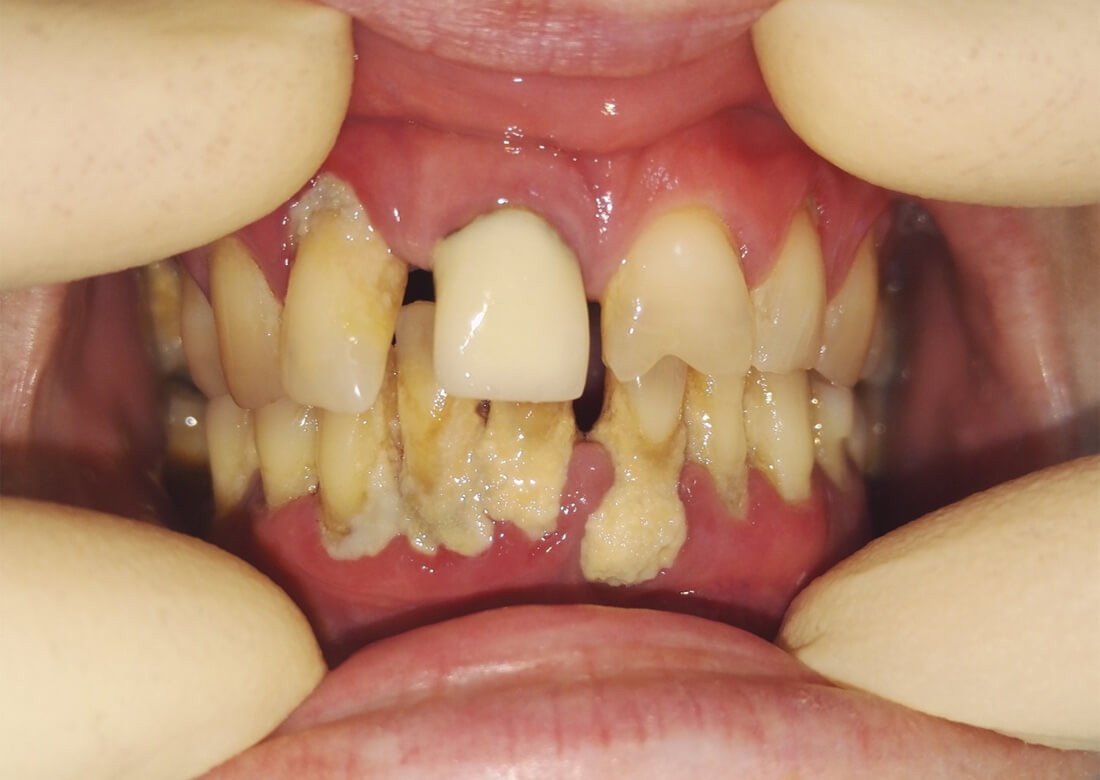

Пациентке нашей клиники требовалось устранить налёт на поверхности зубов. Врач-гигиенист Саражинская Валерия Владимировна провела осмотр полости рта и предложила провести процедуру профессиональной чистки зубов с помощью эффективных методик.

После процедуры пациентка осталась довольна результатом и внешним видом своих зубов. Проблема была успешно решена.

Всего за 1 визит Валерия Владимировна провела необходимые манипуляции и зубы пациентки стали гладкими, белыми и блестящими!

Процедура профессиональной гигиены включала следующие этапы:

• Осмотр и оценка состояния полости рта;

• Удаление зубного камня с помощью ультразвукового скайлера

• Устранение мягких зубных отложений аппаратом Air Flow;

• Полировка зубов специальной пастой и щётками.